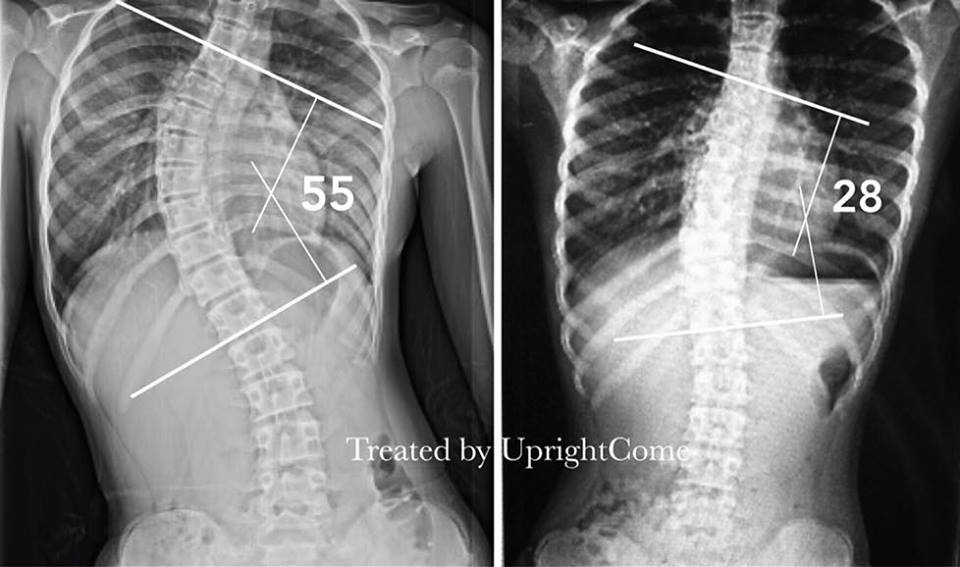

A 12-year-old girl with severe scoliosis in 55 degrees from Taipei

2018-11-16A 12-year-old girl with severe scoliosis in 55 degrees from Taipei The X-ray after thre ...